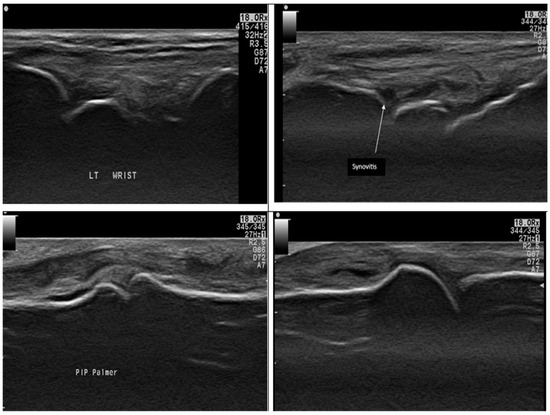

2.5. Musculoskeletal Ultrasound Examination

- Bruyn, G.A.; Iagnocco, A.; Naredo, E.; Balint, P.V.; Gutierrez, M.; Hammer, H.B.; Collado, P.; Filippou, G.; Schmidt, W.A.; Jousse-Joulin, S.; et al. OMERACT Definitions for Ultrasonographic Pathologies and Elementary Lesions of Rheumatic Disorders 15 Years On. J. Rheumatol. 2019, 46, 1388–1393. [Google Scholar] [CrossRef]

- Di Matteo, A.; Mankia, K.; Azukizawa, M.; Wakefield, R.J. The role of musculoskeletal ultrasound in the rheumatoid arthritis continuum. Curr. Rheumatol. Rep. 2020, 22, 41. [Google Scholar] [CrossRef]